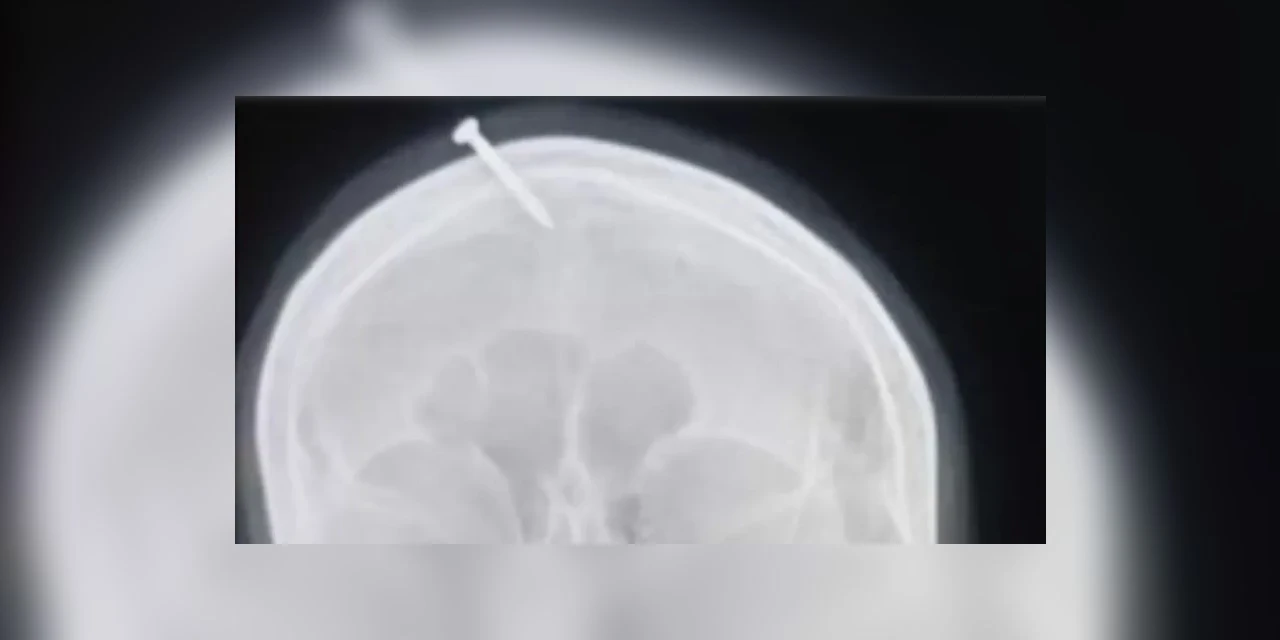

Grávida martela prego na testa após dica de curandeiro para ter menino

Autoridades da cidade paquistanesa de Peshawar procuravam nesta quarta-feira (09/02) um falso curandeiro que aconselhou uma mulher grávida a martelar um prego na testa para que pudesse dar à luz um menino. Embora o prego tenha penetrado o crânio da mulher, não atingiu o cérebro, informou o neurologista Haider Suleman, que tratou a vítima no Hospital Lady Reading. "Ela disse que uma outra mulher de sua localidade fez o mesmo [martelou um prego na testa] e deu à luz um menino, embora o ultrassom tenha mostrado que o feto era uma menina", declarou Suleman à agência de notícias paquistanesa Dawn. Consultar curandeiros é um hábito comum no Paquistão para pessoas que buscam soluções espirituais para seus problemas. A maioria desses curandeiros tem ligação com religiões. O incidente chamou a atenção das autoridades depois que o raio x da vítima se tornou viral. A polícia examinou o conteúdo para o caso. "Uma equipe especial foi montada para levar à Justiça o falso curandeiro que brincou com a vida de uma mulher inocente e a fez colocar um prego em sua cabeça, com uma falsa promessa de que ela teria um filho do sexo masculino", escreveu no Twitter o chefe de polícia local, Abbas Ahsan. Ele acrescentou que também investigará por que o incidente não foi relatado à polícia pelo médico que socorreu a vítima.